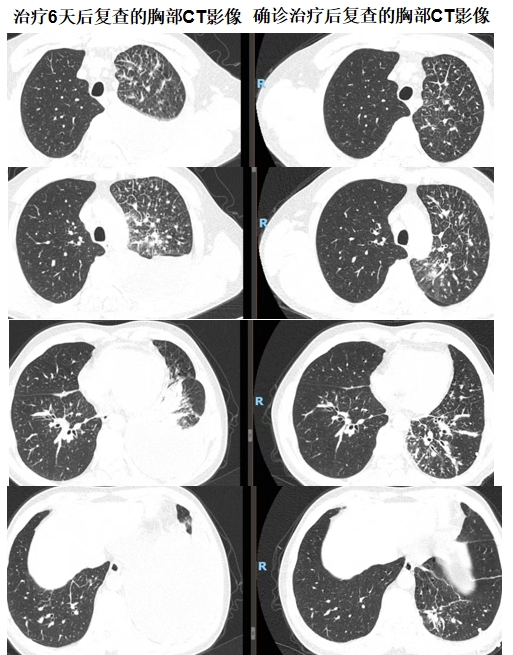

经过六天的规范治疗,患者胸闷、气短症状愈发明显。见此情形,我院肺病科专家团队紧急为患者复查胸部CT。对比入院时的影像资料,发现左肺感染进展,胸腔积液增多,右肺下叶新发感染。肺病科的谢加利主任和艾克东副主任临危不乱,凭借多年积累的丰富临床经验和敏锐的专业洞察力,对患者的病情展开深入细致的分析。他们在仔细研读CT影像时,敏锐地捕捉到一系列异常细节:患者胸水单侧且发展迅速、左肺淋巴管增粗、胸水呈淡血性,结合胸水细菌培养+药敏结果(肺炎克雷伯菌感染)及结合药敏抗炎不佳的情况,考虑肺炎合并肿瘤可能性大。

时间紧迫,分秒必争。当务之急便是获取肺部病变组织的病理结果,才能为后续的治疗指明方向。与患者家属充分沟通后,为患者实施了CT引导下经皮左肺病变穿刺活检术,手术团队凭借精湛娴熟的技术,成功获取了病变组织样本。经过严谨细致的病理检测,最终确诊为左肺腺癌。在全体医护人员的悉心照料与专业治疗下,患者病情迅速得到控制并好转,患者的脸上重新绽放出久违的笑容。